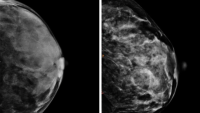

Your team of breast cancer specialists at Columbia Cancer are leaders in the diagnosis, care, and treatment of all stages and types of breast cancer. We understand that no two breast cancer diagnoses are the same. We care for you as a whole person, not just a cancer patient.

Our caregivers see hundreds of breast cancer patients each year and treat all forms of the disease, from the most common to the rarest. We use the power of cutting-edge technology and discoveries made in our labs to provide you with personalized, comprehensive care. And our cancer doctors lead clinical research trials that bring new ideas and new treatments into our clinics.

Your Columbia Cancer team of specialists are leaders in breast cancer care and treatment, offering the newest personalized treatments, including cosmetically sensitive surgery, radiation therapy, and the latest advances in personalized medicine.